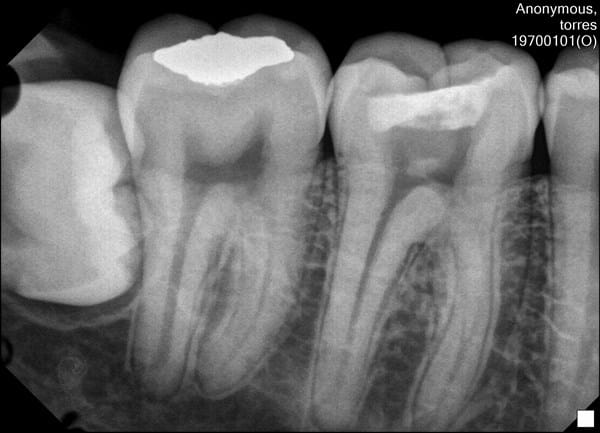

Esta es una radiografía periapical del diente 4.7. O eso aparenta, ya que si se intentaba sacar la 4.6 no se ven los ápices de las raíces.

El diente 4.7 tiene una restauración oclusal seguramente de amalgama. No se observan caries.

Lo que se ve en el diente 4.8 (tercer molar) se llama saco pericoronario. Una vez que el diente se ha desarrollado por completo dentro de la mandíbula, la parte coronal del folículo se denomina saco pericoronario que persiste junto a la corona de los dientes sin erupcionar o impactados. Que es el caso, ya que este diente esta impactado. Creo que podría estar semierupcionado.

Como esta es una imagen 2D no podemos saber de que manera se encuentra en relación al diente de adelante, para eso necesitaríamos otro examen imagenológico si queremos extraerlo.